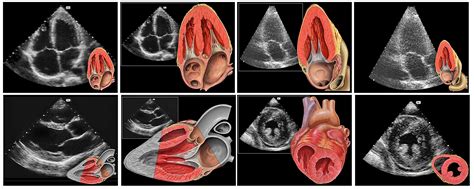

Existujú rôzne typy echokardiografie:

- Transtorakálna echokardiografia (TTE): Senzor sa umiestňuje na hrudnú stenu pacienta a cez ňu sa vizualizujú srdcové štruktúry a funkcie. Je neinvazívna a bezbolestná.

- Transezofageálna echokardiografia (TEE): Ultrazvuková sonda sa zavádza do pažeráka cez ústa alebo nos. Umožňuje detailnejšiu vizualizáciu srdcových štruktúr, najmä chlopní, aorty a srdcových prepážok, pričom sa vyhýba obmedzeniam spôsobeným kosťami hrudníka a pľúcami. Toto vyšetrenie je invazívnejšie a vyžaduje si špecifickú prípravu.

- Dopplerovská echokardiografia: Táto metóda sa zameriava na hodnotenie prietoku krvi v srdci a cievach. Využíva Dopplerov jav, ktorý umožňuje merať rýchlosť a smer prúdenia krvi.